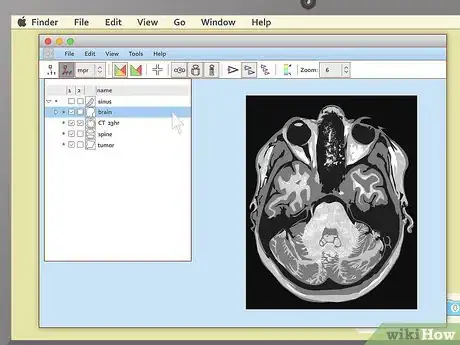

3Use cross-sectional views to spot abnormalities in brain MRIs. MRIs of the brain tissue are often used to check for brain tumors, abscesses, and other serious problems that can affect the brain. The easiest way to see these things is usually to choose the cross-sectional view, then descend slowly from the top of the head downward. You're looking for anything that's not symmetrical — a dark or light patch that's on one side but not the other is cause for concern.

- Brain tumors often take the form of round, golf ball-like growths in the brain which will usually show up as either bright white or dull grey surrounded by a ring of white. However, other brain problems (like multiple scleroses) can also have a whitish appearance, so this alone may not be a sign of a brain tumor.